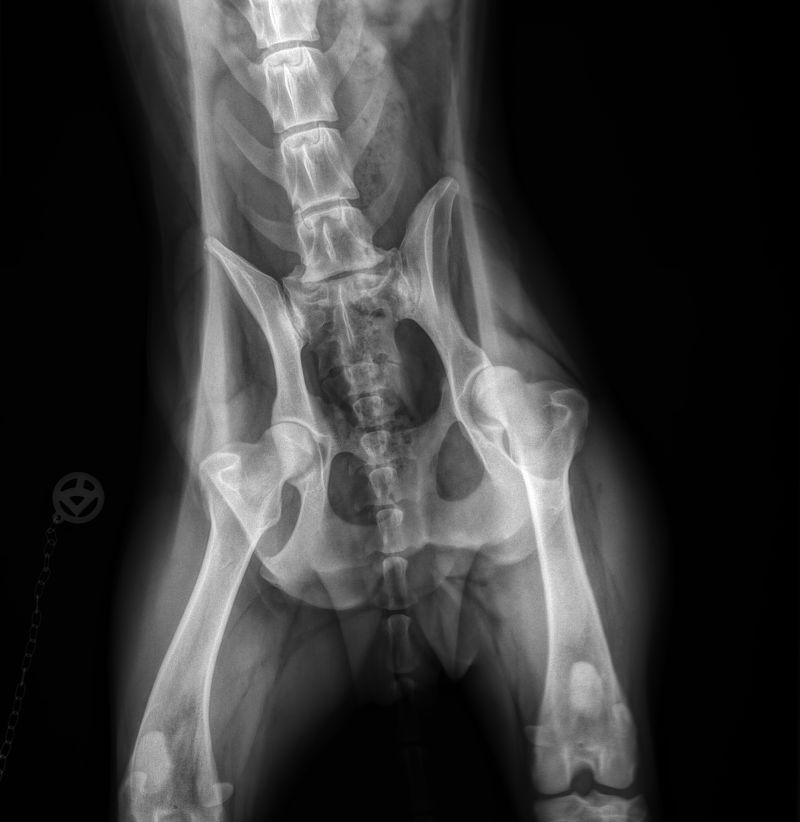

Röntgen Novenber 2016 nach heftigen Rückenschmerzen

Ergebnis: beginnende Spondylose. Dr. Eckes empfiehlt viel Schmerzmittel und kein wildes Toben mehr. Ich finde dank Facebook eine Frau, die in Akupunktur perfekt ist (Heike Dobersch aus Nümbrecht). Sie stellt fest: so ziemlich alle Wirbel sind verschoben. In 10 Sitzungen wird das behoben. Angeblich bildet sich die Spondylose zurück...??? Aber bis heute kein derartiger Anfall mehr.